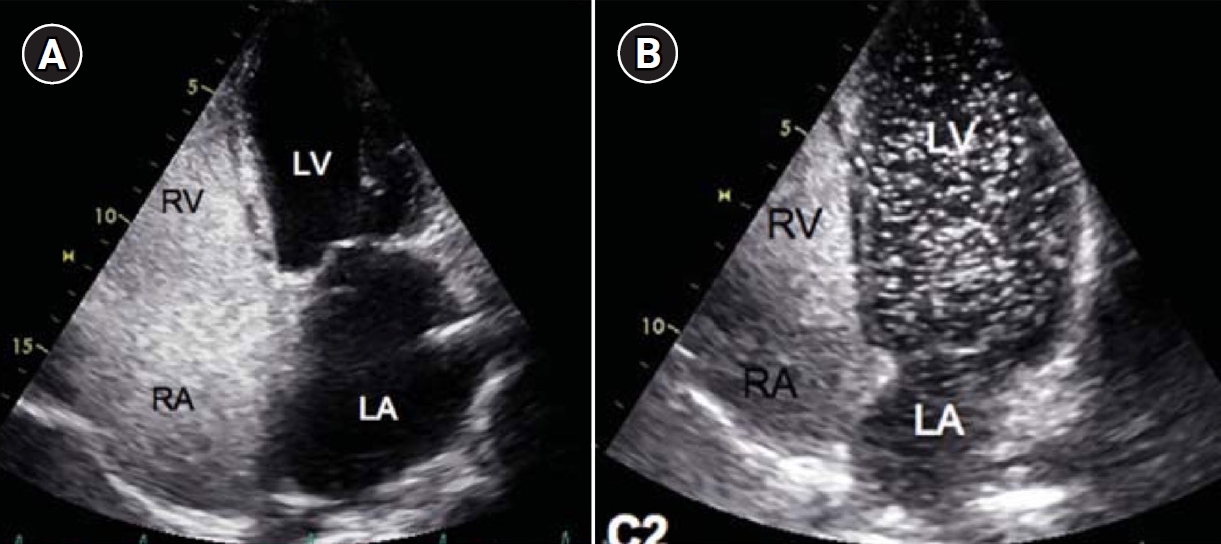

- How I Do It Mar 5, 2026 Catheter-directed sclerotherapy for ovarian endometriomas Byung Soo Im, Ji Hoon Shin Korean J Interv Radiol 2026;31(1):43-45.